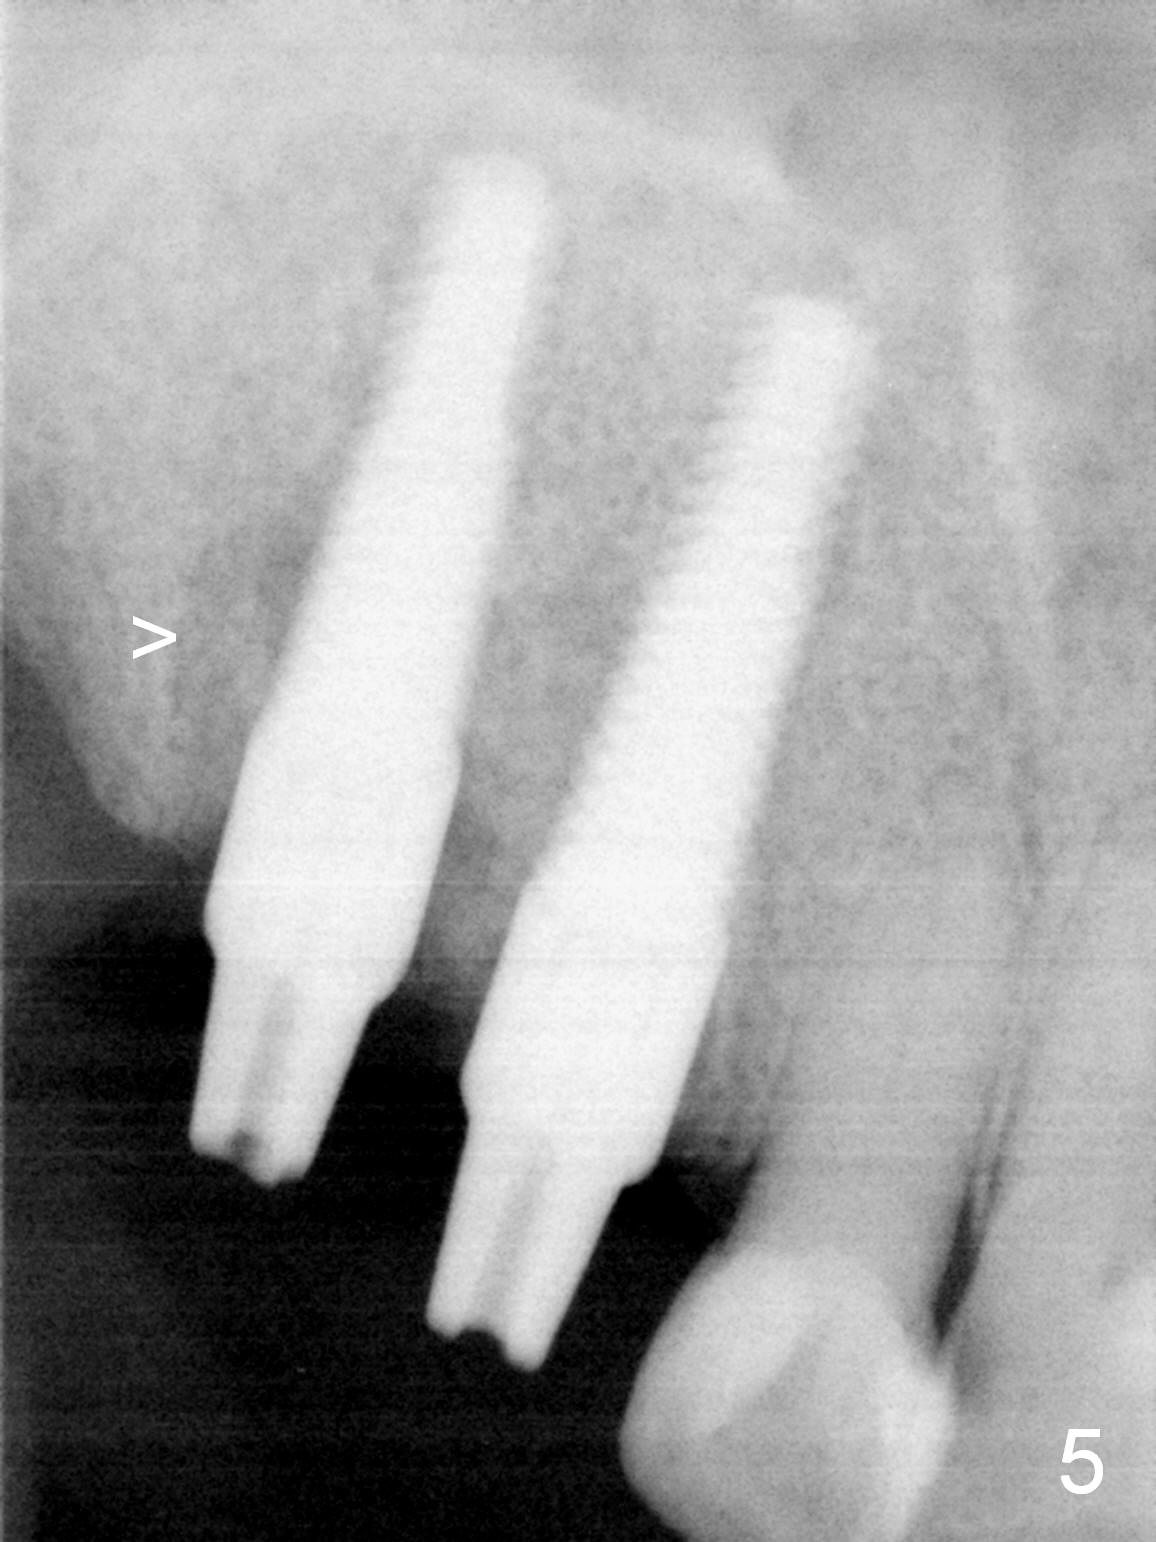

Several of CK's upper teeth (apparently in cross bite) are to be restored with implants (Fig.1).  The first two are #5 and 6; note the oval roots (Fig.2).  After extraction, and curettage, osteotomy starts in the palatal aspect of each socket.  The 1st intraop PA shows that the trajectory at #6 is incorrect (Fig.3).  After adjustment, osteotomies look parallel (Fig.4: D: 3.5x20 mm drill; T: 4.5x20 mm tap).  This suggests how important it is to use parallel pins to check initial osteotomies for neighboring implants (Fig.3).  The trajectory of the implants remains acceptable (Fig.5: 4.5x20 mm with insertion torque »60 Ncm); so is the position of the implants (as palatal as possible; Fig.6 (*: bone graft)).   Immediate provisionals are fabricated in cross bite.

Bone density in the distal gap of #5 appears to have increased 3 months postop (Fig.7).  Prior to definitive restoration cementation (3.5 months postop), the buccal plate does not collapse (Fig.8).  There is no occlusal contact of the new restorations (Fig.9 *), probably due to bite discrepancy (Fig.10,11).